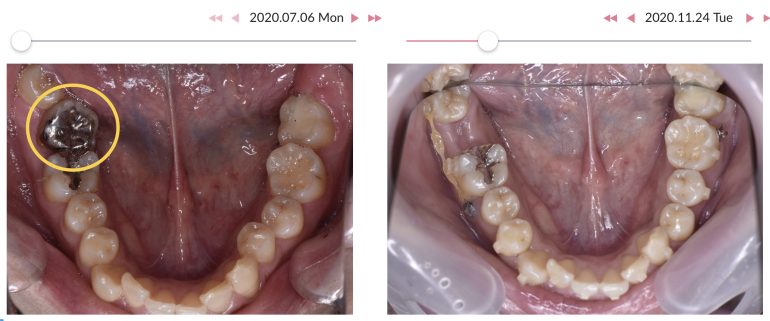

こちらの患者様は、○で囲ってある歯の状態が良くなかった為、抜歯して代わりに親知らずが前に来るように治療を計画しました🦷

器具を設置して引っ張られるようにしながら、全体的にインビザライン矯正を進めていくことに。

約2年でここまでの変化が見られました✨